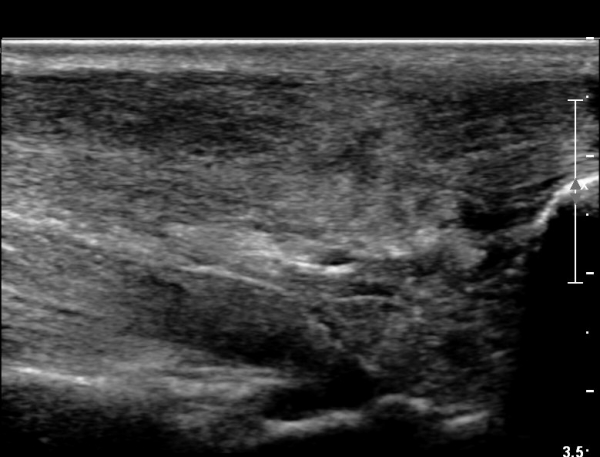

³»Ãø ºñº¹±Ù Á¾´Ü¸é°Ë»ç¿¡¼­ ³»Ãø ¹èº¹±Ù ¸»´ÜºÎ ÆÄ¿­°ú °¡Àڹ̱٠½ÉºÎ¿¡ ¼ö¾×Àú·ù°¡ °üÂûµÊ(»çÁø 1, 2).

¾ÆÅ³·¹½º°Ç Á¾´Ü¸é°Ë»ç¿¡¼­ ¾ÆÅ³·¹½º°Ç ¸»´ÜºÎ¿¡ ¾ÆÅ³·¹½º°ÇÀÇ Àú¿¡ÄÚºÎÁ¾, ±¹¼ÒÀû ¿¬°á¼º ¼Ò½Ç,

¹ß¸ñ°üÀý ÈĹæºÎ¿¡ ¼ö¾×Àú·ù°¡ °üÂûµÊ(»çÁø 3, 4, 5).